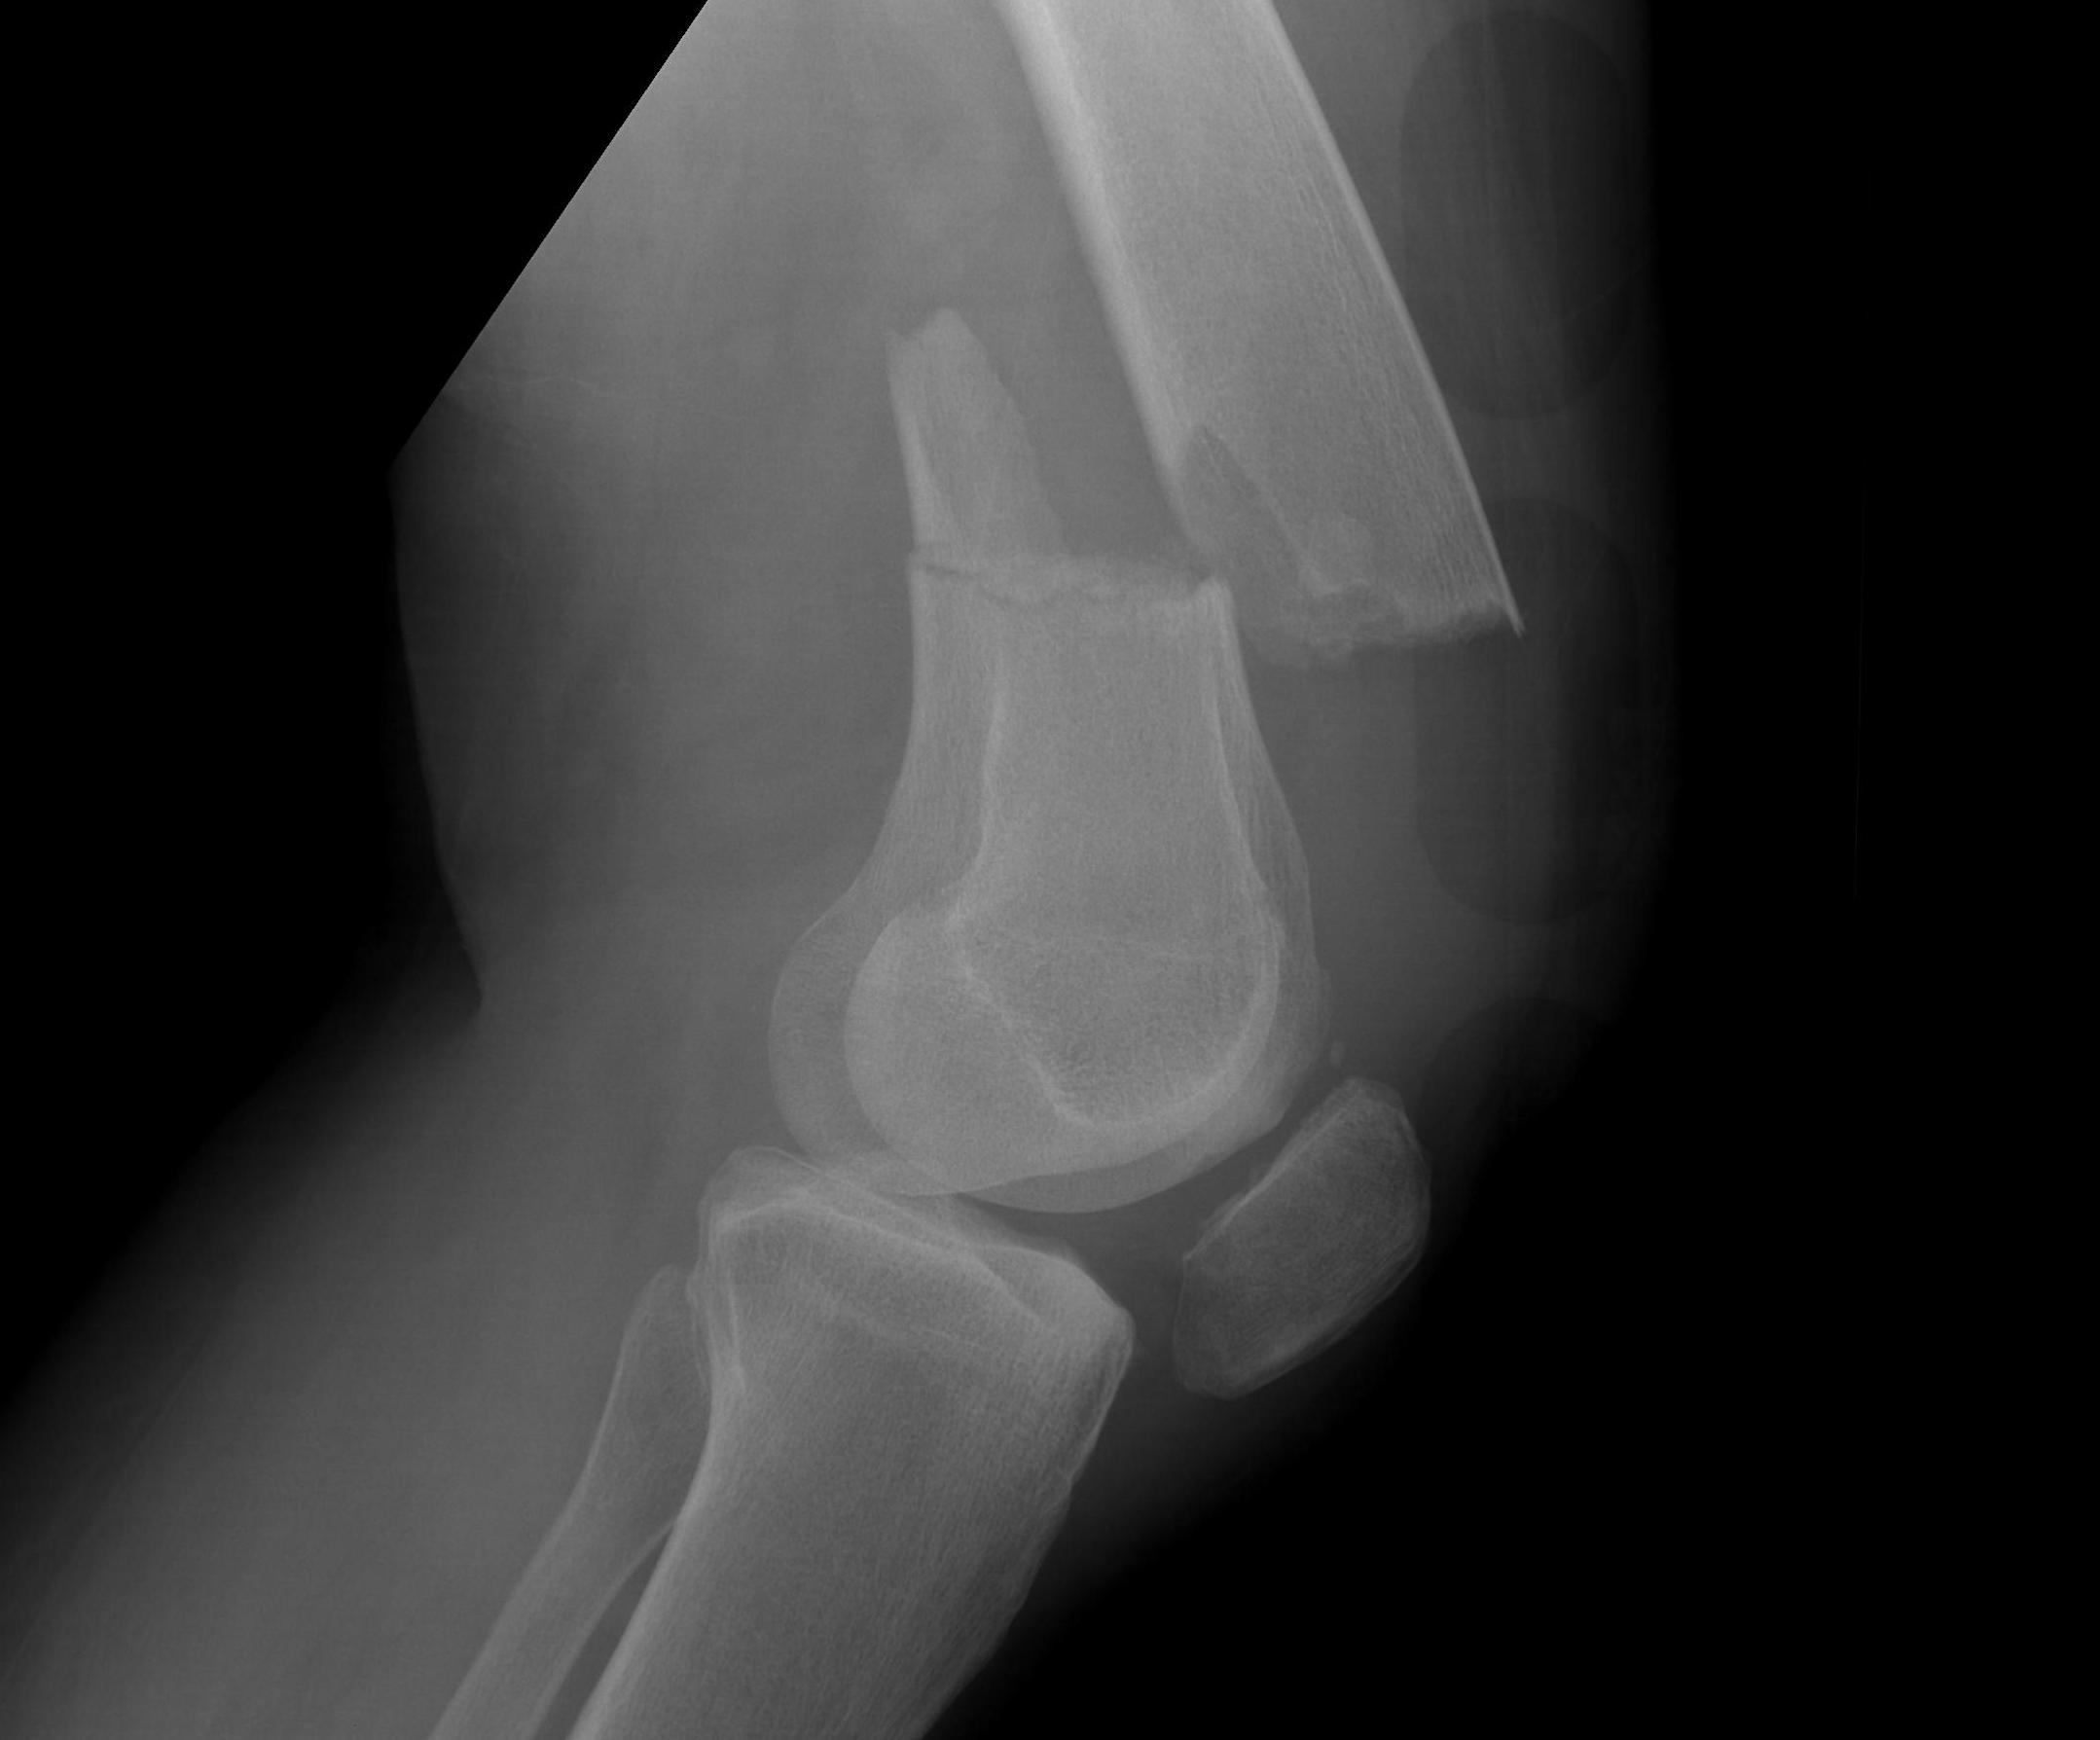

Xray

AO Type B1 & B2: Partial articular

![]()

Lateral split fracture distal femur